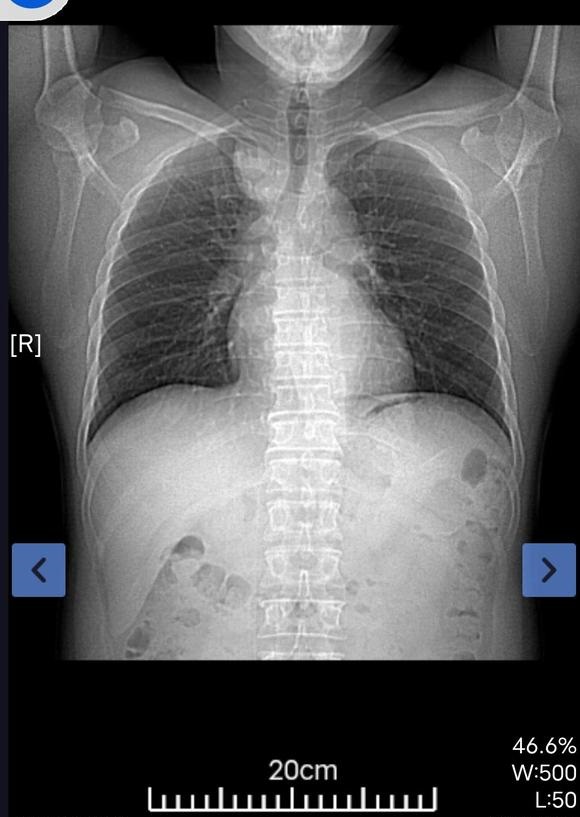

镜 02022-04-02 患者爸爸查出来肺腺癌晚期,双肺转移,大量胸腔积液,在医院抽取了积液,胸骨和肋骨好像也有转移,因为没有基因突变没法吃靶向药。一...